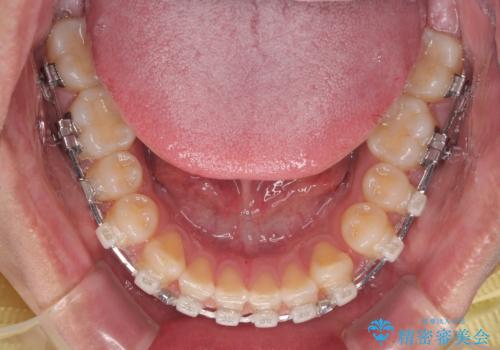

- クリアブラケット

- 1年7ヶ月

- 10-30回

舌癖を改善するためのトレーニングを行いながら、ワイヤー装置を用いて前歯の隙間を閉じていくこととしました。